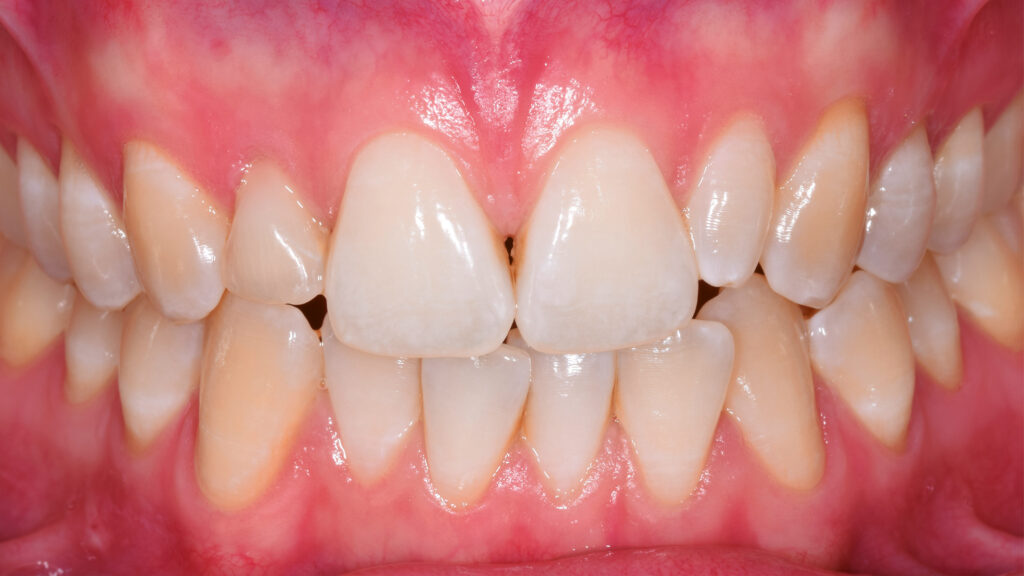

Ein Blick auf die Ausgangssituation (Abb. 1) verdeutlicht die Problematik bei diesem jungen Patienten. Der Milchzahn in regio 12 ist stark verfärbt. Zusätzlich beeinträchtigt der verkleinerte Zahn 22 (Mikrodontie) das ästhetische Bild. Auch der Gingivaverlauf erscheint unharmonisch. Abbildung 2 zeigt die Situation nach kieferorthopädischer Erstbehandlung. Während dieser Behandlungsphase konnte im Frontzahnbereich Platz für das Implantat (TiUltra, Nobel Biocare, Zürich, Schweiz) regio 12 und für das Keramikveneer an Zahn 22 geschaffen werden. Dies bildet die Grundlage für ein natürliches und harmonisches Erscheinungsbild.